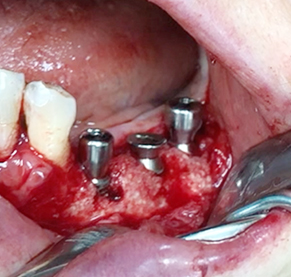

Simultaenous bone grafting for implants

Partial edentulous clinical cases

Implants/Bone Grafting